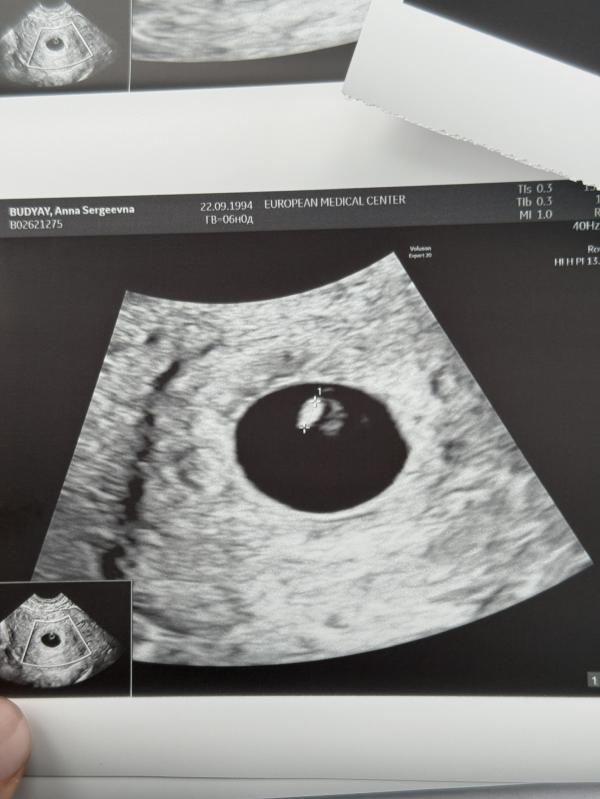

Сегодня было узи :)

Врач: Кан Наталья Енкыновна

Вести беременность буду в ЕМС.

Все хорошо.

Прикрепился высоко. 🫶🏻

Сказали поздняя овуляция (длинный цикл), условно зачатие было в ~ 20 числах октября.

Послушают через 2 недели.